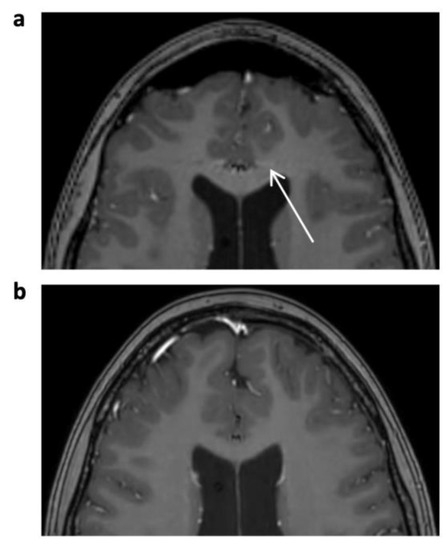

A significant decrease in disruptive artifacts was noted for CS 3D T1 TFE pre-contrast (overall p < 0.001) and post-contrast (overall p < 0.001) images, which is mainly attributable to a reduction in physiological and technical artifacts over the basal ganglia and the cortex. Ghosting and pulsation artifacts of vascular structures were eliminated (p = 0.002 for pre-contrast, p < 0.001 for post-contrast 3D T1 TFE; see Figure 1), followed by a reduction in grid-like reconstruction artifacts (p = 0.008 and p = 0.029, respectively; see Figure 2).

Figure 1.

Enhanced 3D T1 TFE images of a 12-year-old male patient with non-germinomatous germ cell tumor (not shown). Pulsation artifact of anterior cerebral artery in phase-encoding direction noted in SENSE 3D T1 TFE ((a), arrow); not seen in follow-up imaging with CS 3D T1 TFE (b).